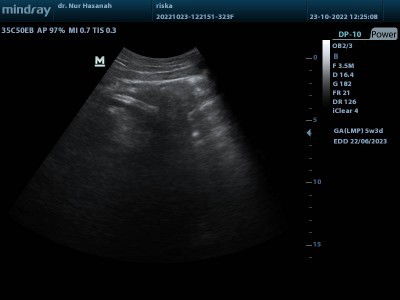

Assalamualaikum bunda bunda, saya menikah desember 2021, fositif hamil awal maret 2022, terus saya keguguran 14 mei 2022 tanpa curetase, juni saya haid seperti biasa, terus dari 19 juli saya haid lagi sampai 15 september bulan kemarin, 2 bulan selama haid itu cuman 1 hari berhenti, terus Hb sama suami setelah seminggu berenti dari haid, seminggu dari Hb saya tespek hasil nya negatif, terus tanggal 20 kemarin saya tespek lagi hasil nya garis 2 tegas, berobat ke bidan belum tau katanya usia janin nya berapa minggu, terus suruh berobat lagi bulan depan dan tespek lagi untuk memastikan lagi hamil atau ngga nya, saya jadi takut bun, apakah ada yang sama seperti saya, jadi fikirannya kemana mana đ„ș#seriusnanya